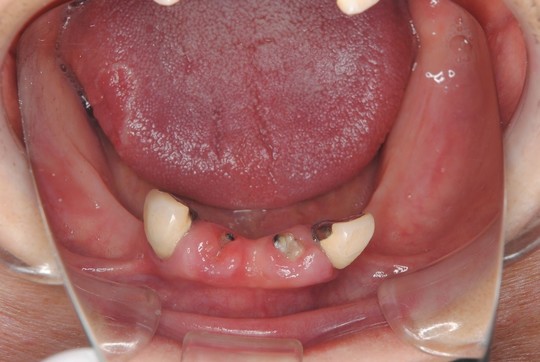

治療前

悪いところを治して上下の義歯を新しくしたいとのことで来院されました。

入れ歯に関しては金具が目立たない入れ歯にして欲しいとの要望がありましたので下の部分入れ歯をノンクラスプ義歯で製作しました。また、しっかりと安定して噛めるようにするため義歯は金属フレームで補強しました。